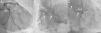

A 74-year-old man, with a history of heavy smoking, presented with unstable angina (Figure 1). Dobutamine stress echocardiography showed ischemia in the right coronary artery territory. Coronary angiography revealed no obstructive epicardial disease in the left dominant circulation (Figure 2A); the right coronary artery (RCA) was a small caliber and tortuous vessel, with only minor atheroma. However, an abnormal vessel arising from the proximal RCA was noted (Figure 2B and C), confirmed as a fistulous connection to the left atrium by multislice computed tomography, which also excluded other vascular anomalies (Figure 3). This was deemed to be causing a coronary steal phenomenon. Exercise myocardial perfusion imaging under anti-ischemic therapy excluded residual ischemia and the patient was successfully conservatively managed (Figure 4).

(A): coronary angiography depicting no obstructive epicardial disease in the left dominant coronary circulation. (B and C): the right coronary artery was a small caliber vessel, with significant tortuosity in its proximal segment, but with no obstructive disease. An abnormal vessel was noted (arrows) arising from its proximal course and heading left, toward a posterior-superiorly located structure. LAD: left anterior descending artery; LCx: left circumflex artery; RCA: right coronary artery.